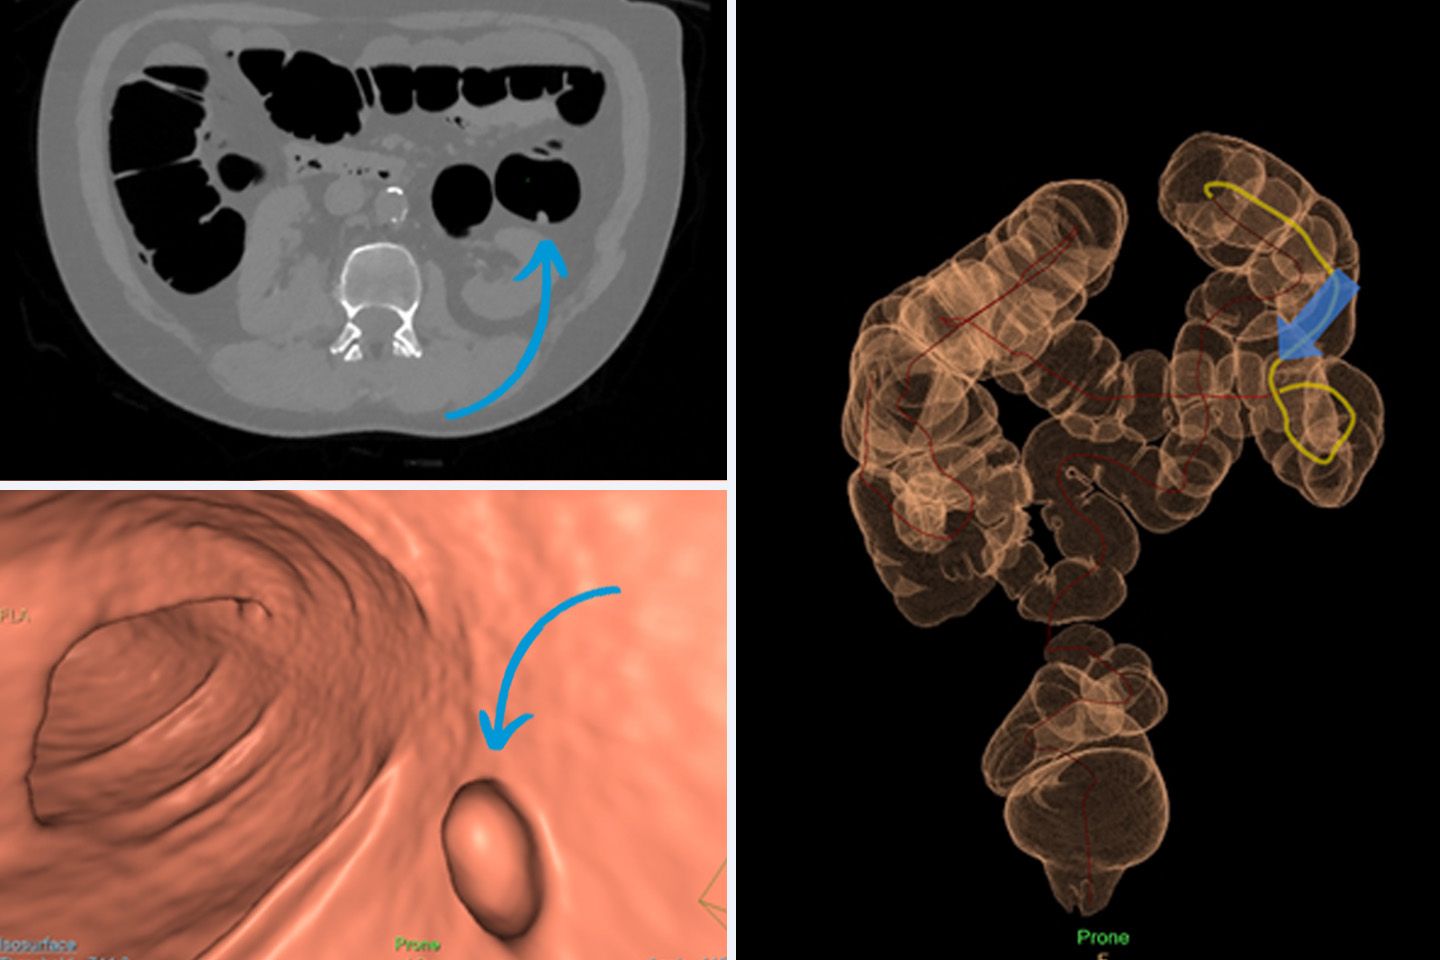

Oben links: Klassisches Schichtbild eines Darms mit Polypen.

Unten links: Die virtuelle Koloskopie ermöglicht eine dreidimensionale Darstellung des Darms inkl. Polypen.

Rechts: Anhand der Übersichtsaufnahme kann die genaue Lokalisation des Polypen in der virtuellen Aufnahme bestimmt werden.